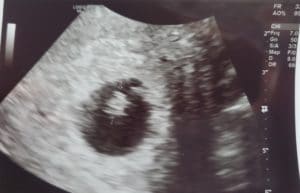

Report From Walla Walla Washington: Baby Is In The Right Place!

Baby Made It To The Uterus!

My baby is in the uterus, at 6 weeks 4 days. Heart rate of 127.

Patient age: 36

Tubal ligation type: Coagulation (burned)

Patient hometown: Walla Walla, Washington